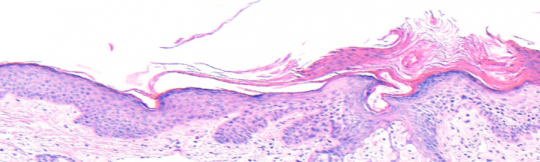

VA38: Upper Forehead, Left of Midline, Actinic Keratosis, Hypertrophic

- Arrows indicate base of epidermal thickening

VA36: Upper Forehead, Left of Midline, Adjacent, Normal